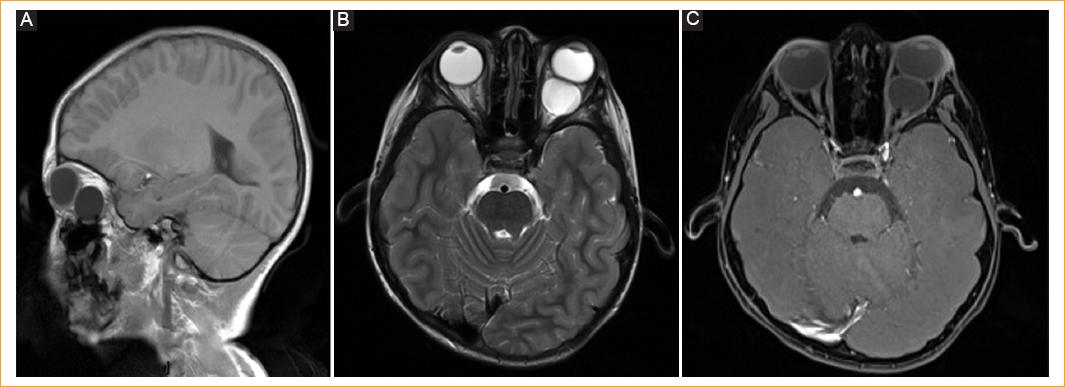

La tomografía computarizada (TC) reporta una lesión retroocular hipodensa heterogénea que remodela la pared lateral de la órbita. La resonancia magnética (RM) de encéfalo muestra una lesión retroocular, intraconal, hipointensa en T1 e hiperintensa en T2 que refuerza muy poco con el medio de contraste, desplazando el globo ocular hacia delante (Fig. 2).

Figura 2 Resonancia magnética. A: en T1 sagital se identifica una imagen hipointensa retroocular de 2.1 cm (transverso) × 1.8 cm (rostrocaudal) × 2.1 cm (longitudinal) que desplaza el globo ocular en sentido anterior, de contornos lisos continuos y contenido homogéneo. B: en T2 axial, la lesión muestra comportamiento hiperintenso con interfase con la pared posterior del globo ocular. C: en T1 axial con gadolinio se observa la lesión con poco reforzamiento de la cápsula, sin compromiso vascular interno.